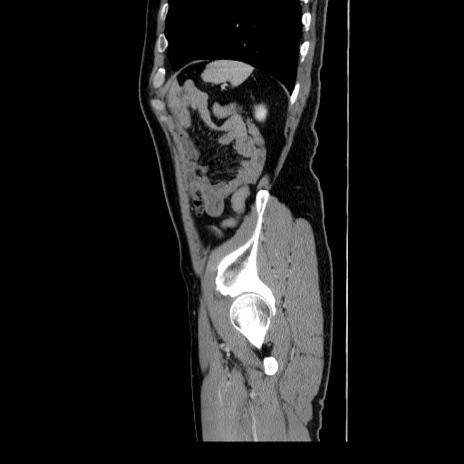

症例34(矢状断像)

【症例】60歳代 男性

【主訴】右鼠径部膨隆

【現病歴】1年程前より右鼠径部膨隆あり。自己にて還納可能だったため放置していた。3時間前より右鼠径部の脱出を認め、還納困難となり受診。

【身体所見】右鼠径部に小児頭大の膨隆あり。弾性硬であり、用手還納は困難。左鼠径部にも膨隆を認める。脱出はなし。